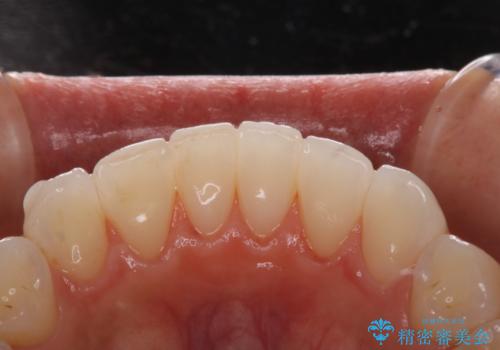

マウスピース矯正(インビザライン)中のPMTC

- インビザラインでの矯正治療中の方です。久しぶりにクリーニングをしたいとのことでした。

PMTC60分コースを行いました。

PMTCは審美的な面だけではなく、虫歯や歯周病予防にもなります。

矯正治療中(ワイヤー・マウスピース共に)虫歯や歯周病予防のためには、お口の中を清潔に保つことが大切です。